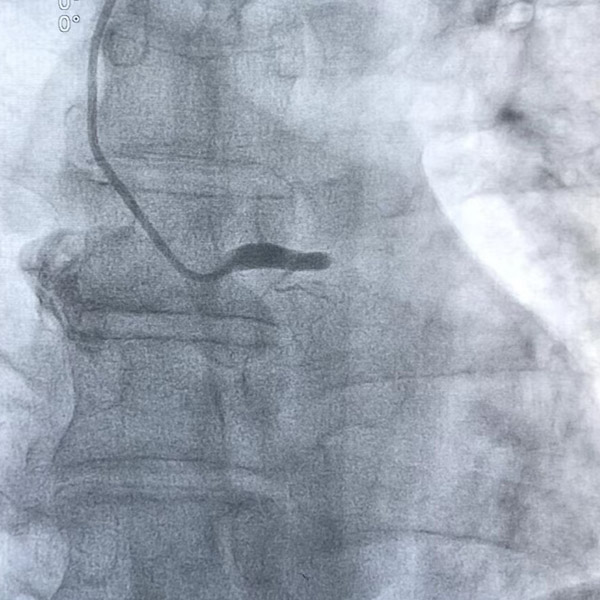

周先生順利被送入介入室,不到10分鐘就做完了心臟造影,結(jié)果令人驚愕——“左主干中遠(yuǎn)端100%閉塞”!

陶林仔細(xì)分析了患者的病情后,當(dāng)機(jī)立斷為患者進(jìn)行手術(shù),一場(chǎng)爭(zhēng)分奪秒的搶奪戰(zhàn)就此拉開(kāi)序幕。介入團(tuán)隊(duì)憑借豐富的臨床經(jīng)驗(yàn),第一時(shí)間就找到了患者的左主干開(kāi)口,如線穿針般細(xì)心地將導(dǎo)絲穿過(guò)病變血管,球囊擴(kuò)張后成功植入支架及時(shí)疏通血管,左主干狹窄解除,血流恢復(fù),整個(gè)過(guò)程不到一個(gè)小時(shí),成功地將患者從死亡線上拉了回來(lái)。